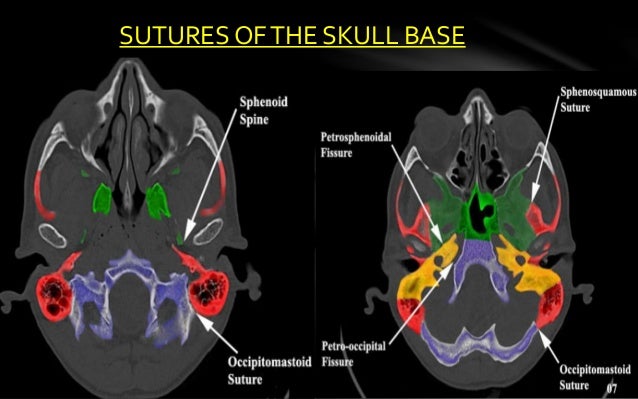

Ct skull base anatomy. You can however go directly to any section using the links below. B axial ct image with color coded overlay shows the skull base bones. The skull base can be evaluated by computed tomography ct which will demonstrate the bony structures of the skull base with its foramina and fissures for vessels and cranial nerves the temporal bone and sinonasal cavities.

Ct anatomy of skull base. Blue central skull base csb purple posterior skull base teal anterior skull base asb. Foramina of the skull base and the structures that pass through them.

Cranial foramina for further details. A axial three dimensional reconstructed ct image with color coded overlay shows the skull base sections. Ct anatomy of skull base.

Blue temporal bones fuchsia nasal bones green ethmoid bone light pink vomer purple occipital bones teal sphenoid bone yellow zygomatic bones. Basic anatomy review the bones sutures and fissures that comprise the skull base. Detailed anatomy enter this module for a more detailed review of skull base anatomy.

Ct is more sensitive in detecting fibro osseous skull base lesions calcification and sclerosis. The module interface is meant to mimic a radiology workstation with adjacent image scrolling via arrow keys and or mouse wheel button. Navigating the skull base identify the petro occipital fissure to navigate the major structures of the skull base.